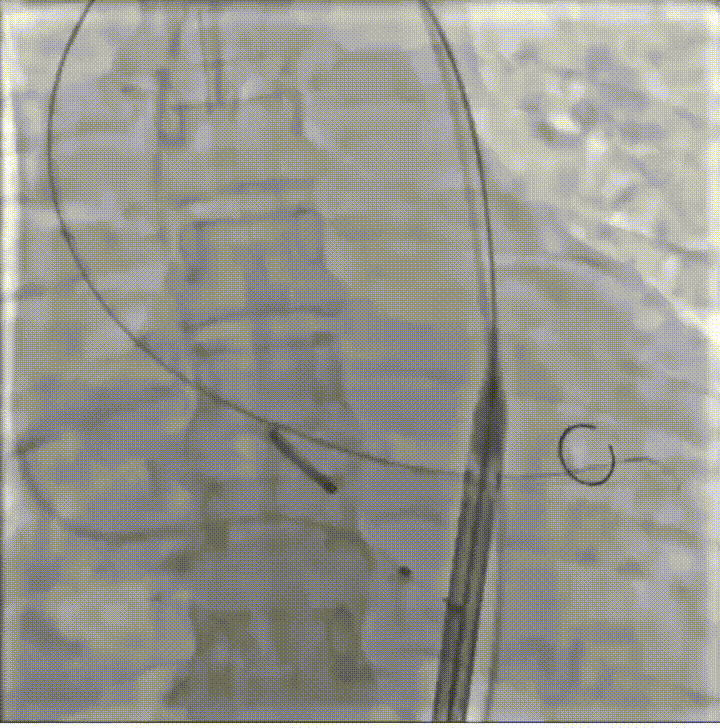

病例概览

患者病史 男性,74y, 因 “发现心脏瓣膜病 1 年,加重伴喘气半年” 入院。门诊检查显示主动脉瓣重度AS并伴轻-中度AR。患者基础疾病较多:胸腹主动脉多发穿透性溃疡、心功能III级等,手术指征明确,但风险极高。 术前CT LVOT- Annulus 倒梯形,对植入瓣膜有挤压位移风险,Annulus直径23.7mm,瓣叶增厚,钙化集中在无冠窦边缘。 左冠脉开口高度可,瓣叶不长、窦部空间较大,无冠脉风险;室间隔膜部较短,有一定PPI风险,心脏角度37.9°;心室较小,有一定循环崩溃风险,术前注意补液。 术前造影角度及入路:血管入路散在钙化、无迂曲;主动脉弓条件好、双侧股动脉直径大、右股穿刺点侧壁存在环形钙化 左右重合位:RAO 7° CAU 21° 右窦中心位:LAO2 1° CAU 1° 手术策略 20mm球囊预扩后植入AV26瓣膜,同时做好预防循环崩溃、传导阻滞的应急预案。 术中挑战 1)球囊预扩:20mm球囊预扩时无明显 “腰征”,但存在少量反流,提示瓣膜钙化与解剖结构对扩张的阻力不均 2)首次释放偏差:第一次定位释放时,瓣膜在 “开花” 过程中下滑约 3mm,工作位观察显示小弯侧瓣周漏较多(深度超过完全覆膜区),需二次调整。 3)二次精准定位:以猪尾导管为参照,将定位点调整至 “猪尾 - 2mm” 处,结合真实窦底深度(较深)重新释放,最终瓣膜位置稳定,瓣周漏显著减少。 术后即刻效果: 瓣膜形态良好,跨瓣压差从术前的 67mmHg 降至 6mmHg,且无明显瓣周漏,冠脉开口通畅; Commisural Alignment 术后即刻超声: Prostyle A®预装干瓣——助力临床最优化解决方案: √ 平衡的径向支撑力:特殊的解剖结构下位置形态良好,术后跨瓣压差大幅降低,血流动力学改善明显; √ 80%可回收设计:支持术中二次调整释放位置,保证精准释放; √ 平衡的收腰设计&Commissural Alignment设计: 为患者后期冠脉PCI保留了生命通道;